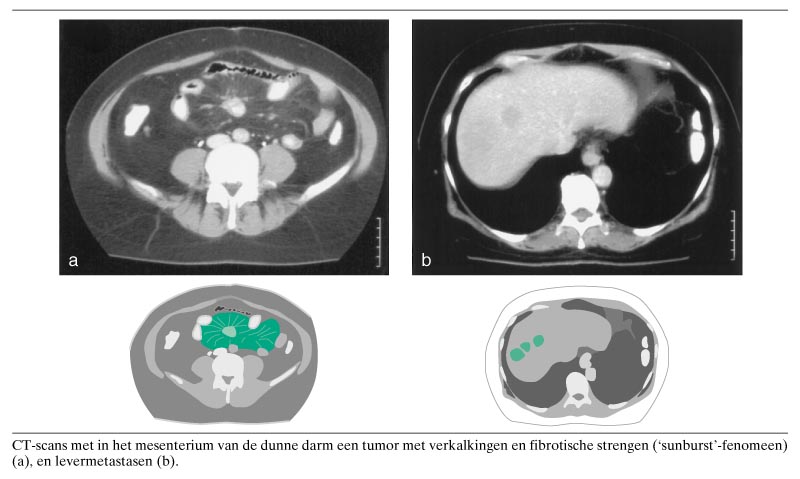

Een 49-jarige vrouw kwam met onbegrepen klachten van braken en diarree op het spreekuur. Bij het lichamelijk onderzoek werden er geen afwijkingen gevonden. Er werd afgesproken laboratoriumonderzoek te doen en tevens echografie van het abdomen te verrichten. Bij het laatstgenoemde onderzoek werden verspreid in de lever kleinere en grote tumoren gezien en mogelijk een wekedelenmassa diep in het mesenterium. Vervolgens werd CT van het abdomen verricht. Daarbij werd een tumor in het mesenterium van de dunne darm gevonden, met verkalkingen (figuur). Dit beeld is typisch voor een carcinoïd; kenmerkend zijn de verkalkingen in de tumor en het zogenaamde ‘sunburst’-fenomeen: radiair verlopende, verdikte neurovasculaire bundels, die uitwaaieren naar de dunnedarmlissen en retractie van het mesenterium en de dunne darm veroorzaken. Tevens waren er multipele levermetastasen (zie de figuur). Differentiaaldiagnostisch kan gedacht worden aan adenocarcinoom, lymfoom, leiomyosarcoom en intraperitoneale metastasen. Carcinoïd is het meest voorkomende primaire neoplasma van de dunne darm (25). Het wordt wel een maligne neoplasma ‘in slowmotion’ genoemd en geeft in de eerste 5 jaar vaak nauwelijks klachten. Bij levermetastasen kan zich het carcinoïdsyndroom voordoen (met cutane ‘flushes’, diarree en bronchospasmen); dit wordt veroorzaakt doordat serotonine, dat door de tumor wordt geproduceerd en dat normaal in de lever wordt omgezet, direct in de circulatie komt. Patiënte onderging een aantal behandelingen met radioactief metajodobenzylguanidine, waarmee het proces bij de laatste follow-up al enkele jaren stabiel was.

Naar de lever gemetastaseerd carcinoïd van de dunne darm.